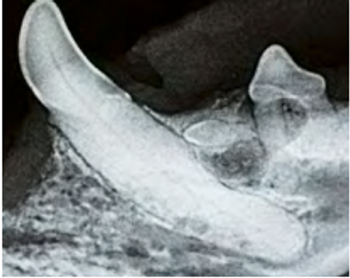

Most of the tooth is located below the gumline and out of view. Intraoral radiography can yield invaluable diagnostic information about your patients’ oral health.